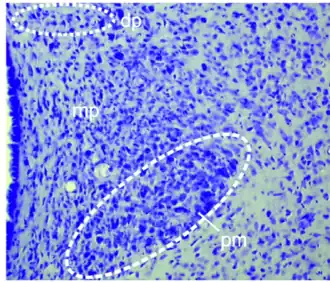

Desde el punto de vista anatómico el hipotálamo se divide en tres zonas principales: medial, lateral y periventricular. Los núcleos se concentran en las zonas medial y periventricular, las más relacionadas con la regulación central endocrina. A la zona lateral se le considera un «relevo» donde están establecidas conexiones del hipotálamo con los elementos encefálicos más rostrales.[37]